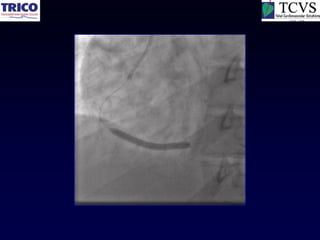

LMCA Bifurcation Rota-Stent

LMCA intervention…

A real nightmare